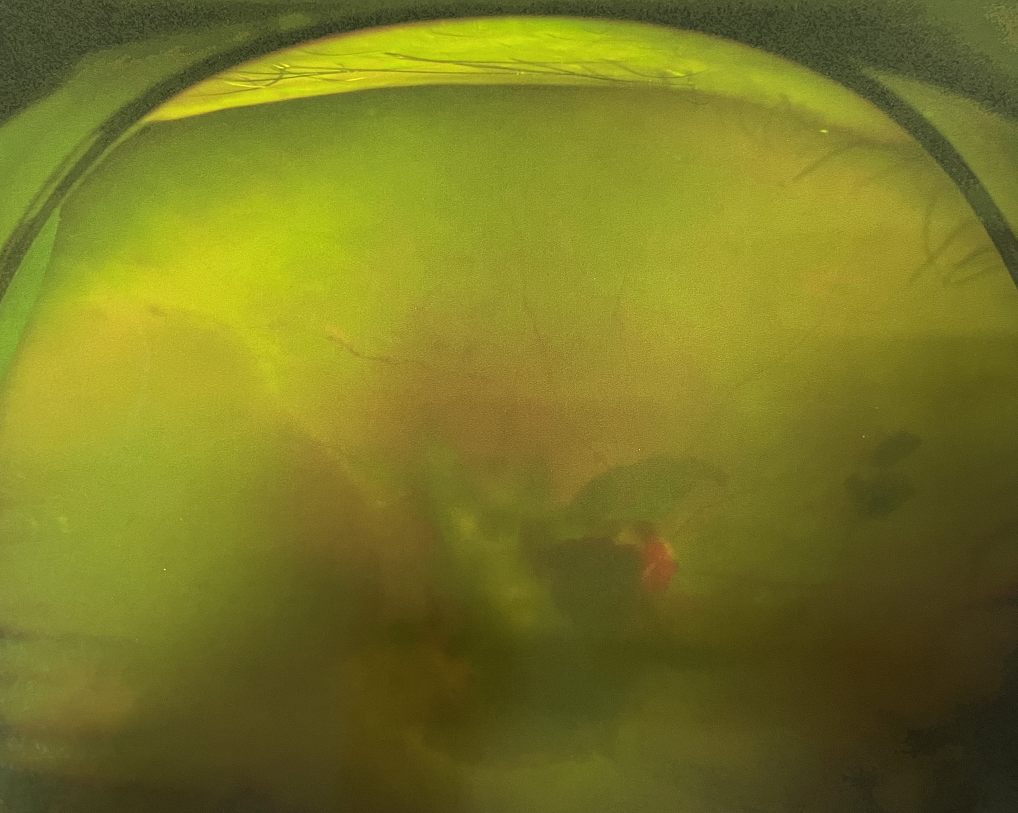

1、眼底出血

高血壓、糖尿病、動脈粥樣硬化、高度近視、視網(wǎng)膜中央靜脈阻塞、脈絡(luò)膜新生血管性疾病等都可能造成眼底出血,引起中心視力下降、視物變形、黑影飄動、飛蚊癥、閃光感等癥狀。